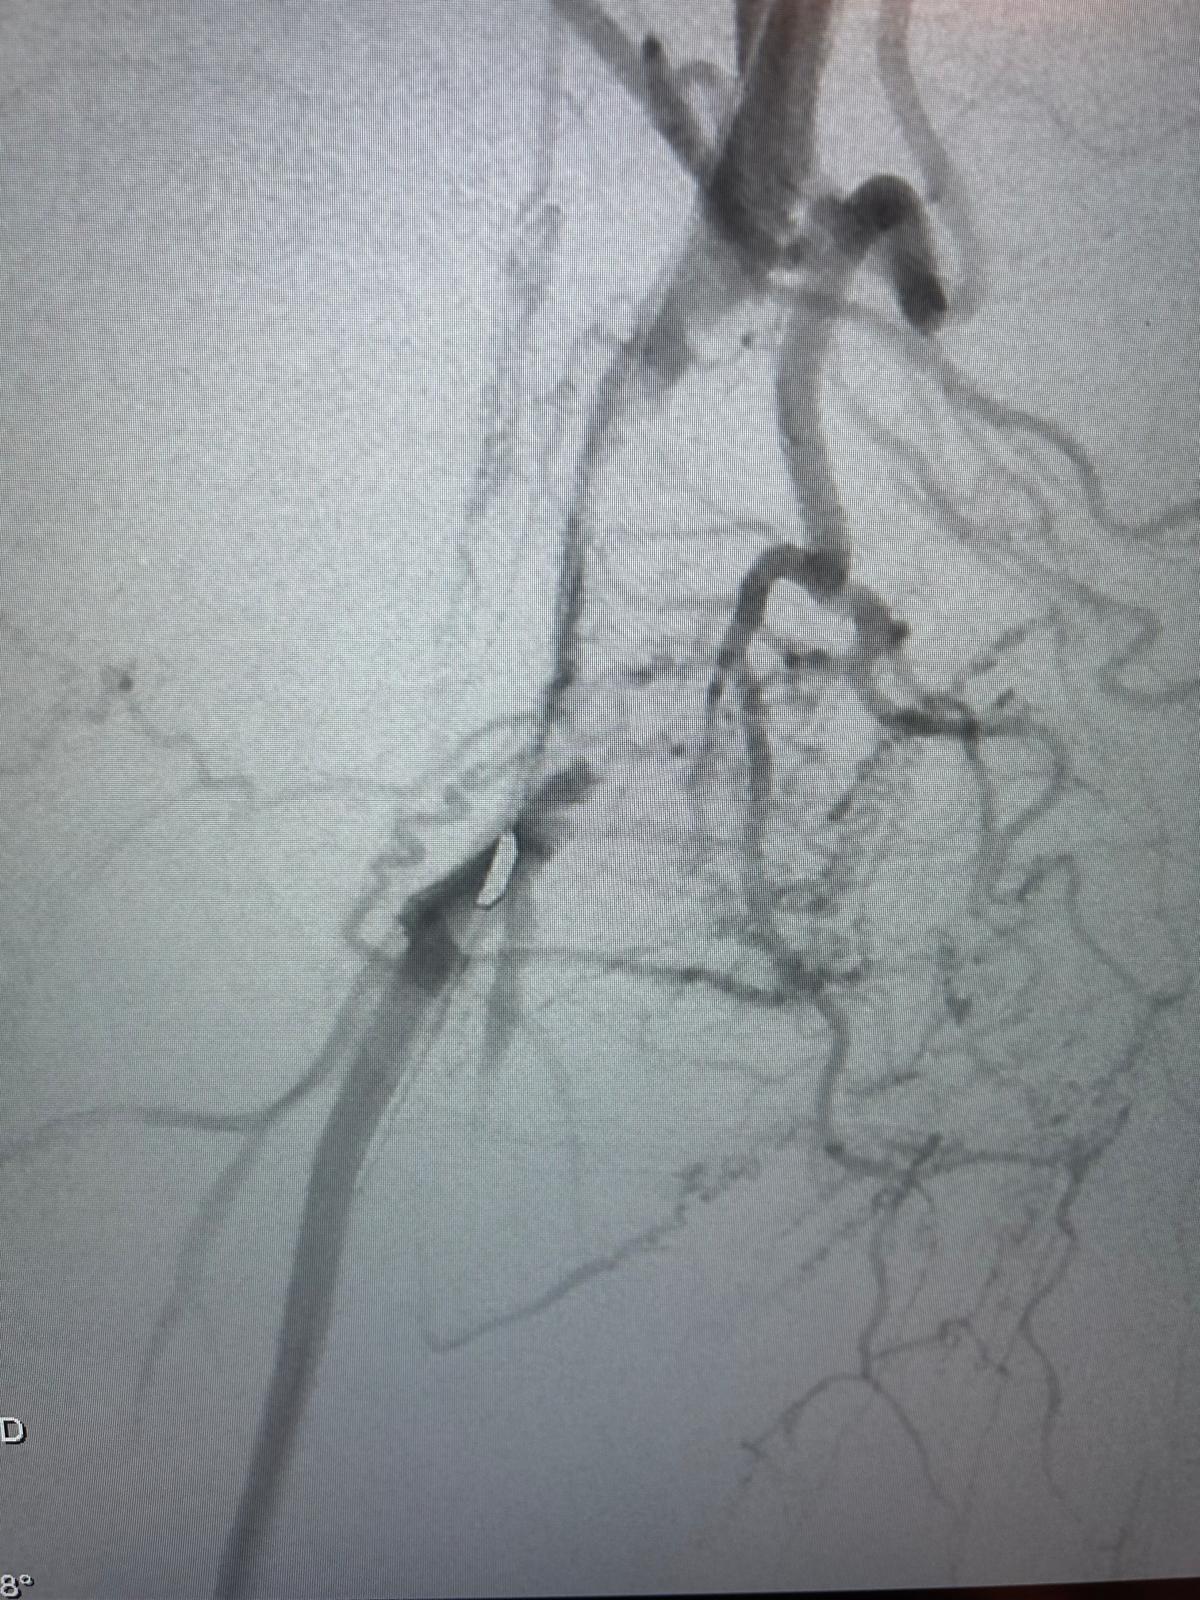

Imagerie pré-opératoire

Angiographie TDM montrant une lésion ectasique de l'artère poplitée rétro-articulaire de 11mm de diamètre, associée à du thrombus circonférentiel entraînant un effet de sténose à plus de 70%, sans calcification.

Altération majeure du lit d'aval artériel : occlusion de la terminaison de l'artère poplitée basse et du tronc tibio-fibulaire, associés à une occlusion proximale des 3 artères de jambe réinjectées à leur tiers proximal par la collatéralité des artères jumelles.

Résultat

Excellent résultat persistant de la recanalisation endoluminale des artères jambières sur le contrôle per-opératoire 15 min après la fin de la recanalisation.

Aucune embolisation distale constatée au niveau des artères du pied.

Disparition de l'ischémie du pied gauche.

Excellent pouls tibial postérieur gauche.